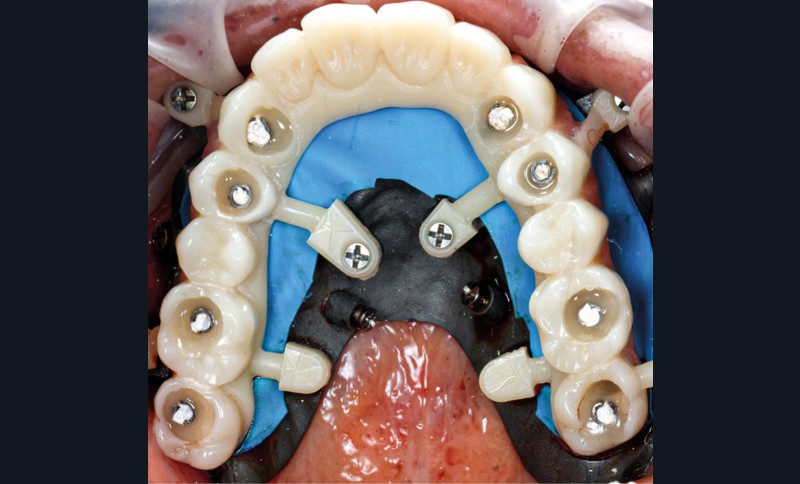

Après une extraction atraumatique des dents résiduelles, nous passons au 3e étage qui est le guide de forage stéréolithographique. La séquence de chirurgie Full guided est passée et les implants ont été torqués entre 40 et 50N.cm2 (fig. 6, 7, 8). Cette stabilité primaire dans les sites d’extraction et des sites greffés a permis la mise en charge immédiate du bridge complet provisoire. Des études cliniques [3, 4, 5] ont montré que la mise en charge immédiate dans les sinus greffés ne pose aucune contre-indication. Le 4e étage est donc celui du bridge provisoire transvissé à l’étage de base et solidarisé en bouche par l’intermédiaire de cylindres provisoires sur piliers MUA, avec une colle duale (GC-LinkForce). L’espace entre les implants et l’alvéole a été comblé par une xénogreffe (Bio-Oss Geistlich). Les profils d’émergence sont travaillés et parfaitement polis. Enfin, le bridge est mis en place, torqué à 20.cm2, équilibré et les consignes postopératoires ont été rappelées à la patiente (fig. 9 et 10).